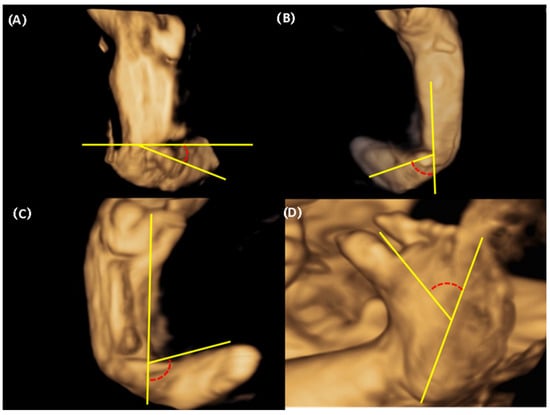

2.3. Sonographic Measurements

| Varus (°) | 60.5 (50.6–71.4) | 46.6 (25.8–52.2) | 0.026 |

| Derotation of CPB (°) | 67.6 (58.2–88.2) | 26.6 (23.0–32.8) | <0.05 |

| Adduction of the forefoot (°) | 22.4 (15.9–30) | 19.7 (17.3–25.0) | 0.649 |